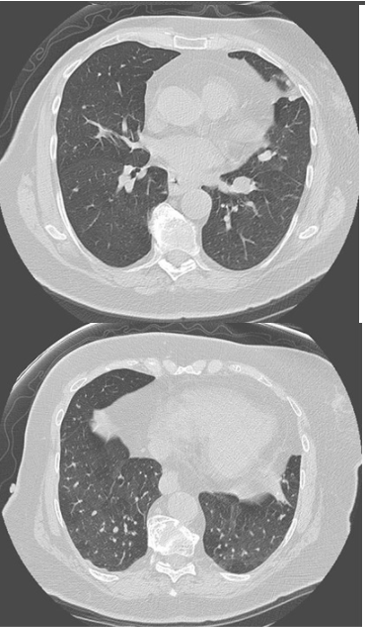

expiratory HRCT images

Diffuse idiopathic neuroendocrine cell hyperplasia (DIPNECH)

multiple small pulmonary nodules and mosaic attenuating from air trapping due to constrictive bronchiolitis

bronchiolar inflammation

Ritalin lung can look like this too